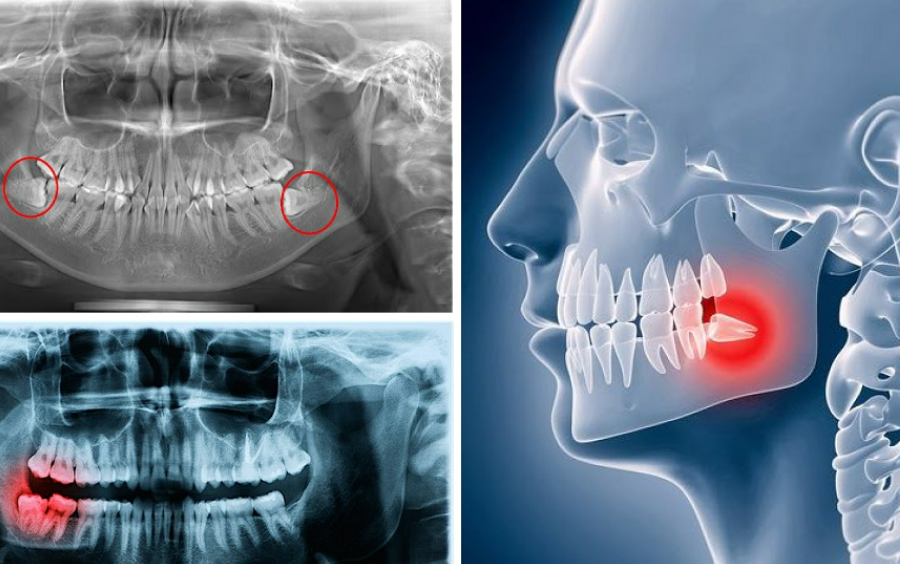

Quyết Định Thời Điểm Nhổ Răng Khôn: Trước Hay Sau Khi Niềng?

Việc nhổ răng khôn trước hay sau khi niềng răng là một câu hỏi thường gặp khi điều trị niềng răng. Sự lựa chọn thời điểm phù hợp sẽ ảnh hưởng đến quá trình và kết quả niềng răng. Cùng SHINING SMILE tìm hiểu qua bài viết dưới đây.